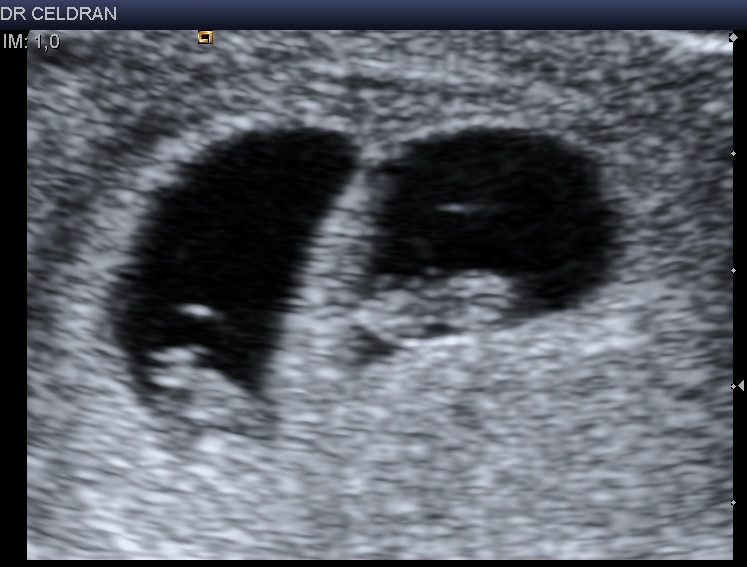

L’image d’une grossesse gémellaire bichoriale : présence du signe du Lambda (paroi épaisse qui sépare les deux sacs). Cette grossesse est parfaitement évolutive avec une activité cardiaque détectable sur les deux embryons (cliquez ici)

. bichoriale (2 sacs gestationnels) et nécessairement une biamniotique

. monochoriale (1 sac gestationnel) le plus souvent biamniotique ou exceptionnellement monoamniotique

Cliquez sur l’image pour la voir en pleine page